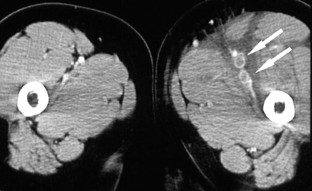

Abb. 1